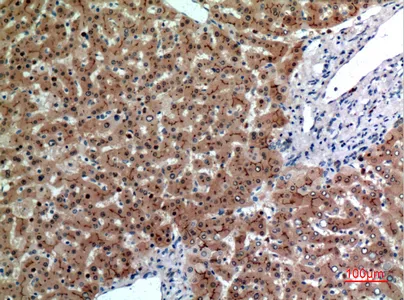

CD244 Rabbit Polyclonal Antibody

Cat: APRab08306

Size1:50μl Price1:$118

Size2:100μl Price2:$220

Size3:500μl Price3:$980

Size2:100μl Price2:$220

Size3:500μl Price3:$980